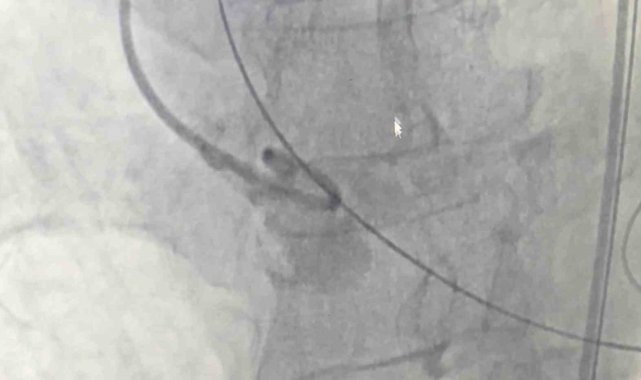

Samsun Eğitim ve Araştırma Hastanesi'nde 80 yaşındaki bir hastaya, nadir görülen dört yaprakçıklı aort kapağı nedeniyle transkateter aort kapak implantasyonu (TAVİ) yöntemiyle başarılı bir operasyon gerçekleştirildi. Operasyon, bu özelliği taşıyan vakalar arasında dünyada 18'inci, Türkiye'de ise ilk olma özelliği taşıyor.

Amasya'nın Merzifon ilçesinde yaşayan Muzaffer Uslu (80), göğüs sıkışması ve baygınlık şikayetleriyle başvurduğu Merzifon Devlet Hastanesi'nden Samsun Eğitim ve Araştırma Hastanesi'ne sevk edildi. Tetkikler sonucu, normalde üç yaprakçıklı olması gereken aort kapağının dört yaprakçıklı olduğu belirlendi. Samsun Üniversitesi Tıp Fakültesi Kardiyoloji Ana Bilim Dalı Öğretim Üyesi Doç. Dr. Mustafa Yenerçağ, kapak değişiminin açık ameliyatla yüksek risk taşıması nedeniyle kapalı yöntem olan TAVİ işlemiyle çözüm sağladıklarını söyledi.

Doç. Dr. Yenerçağ, işlem öncesi yapılan tetkiklerde karşılaştıkları nadir bulgu hakkında ise "Hastanın TAVİ işleminden önce yapılan tetkiklerinde aort kapağının 3 yaprakçıklı olması beklenirken çok daha nadir görülen 'Quadricuspid' adı verilen 4 yaprakçıklı aort kapağı saptadık. Daha önce böyle bir vaka ile karşılaşmamıştık. Literatürleri, akademik çalışmaları inceledik. 4 yaprakçıklı aort kapağının toplumda 100 bin kişide 4 görüldüğünü, taradığımız uluslararası yayınlarda ise 4 yaprakçıklı aort kapağı bulunan sadece 17 hastaya TAVİ işlemi yapıldığını saptadık. Ülkemizden bildirilen vaka örneği bulamadık. Diğer ülkelerde yapılan vakaları detaylıca inceledik. İleri tomografik analizleri yaptık. Vakamıza detaylıca hazırlandık" dedi.

"Doç. Dr. Serkan Sivri, asistan doktorlarımız Berkan Öztürk ve Enes Kaya ile Anestezi Uzmanı Aynur Kaynar hocamızla beraber ekip halinde hastamıza başarılı TAVİ işlemini yaklaşık 50 dakika içerisinde tamamladık. Hastamızı 1 gün yoğun bakımda takip ettikten sonra servis takibine aldık. Nadir görülen bu 4 yaprakçıklı aort kapağına yaptığımız TAVİ işleminin prosedürel detaylarını literatüre kazandırmayı planlıyoruz. Bizden sonra bu nadir vaka ile karşılaşan meslektaşlarımıza yol göstermesi açısından referans olacaktır."